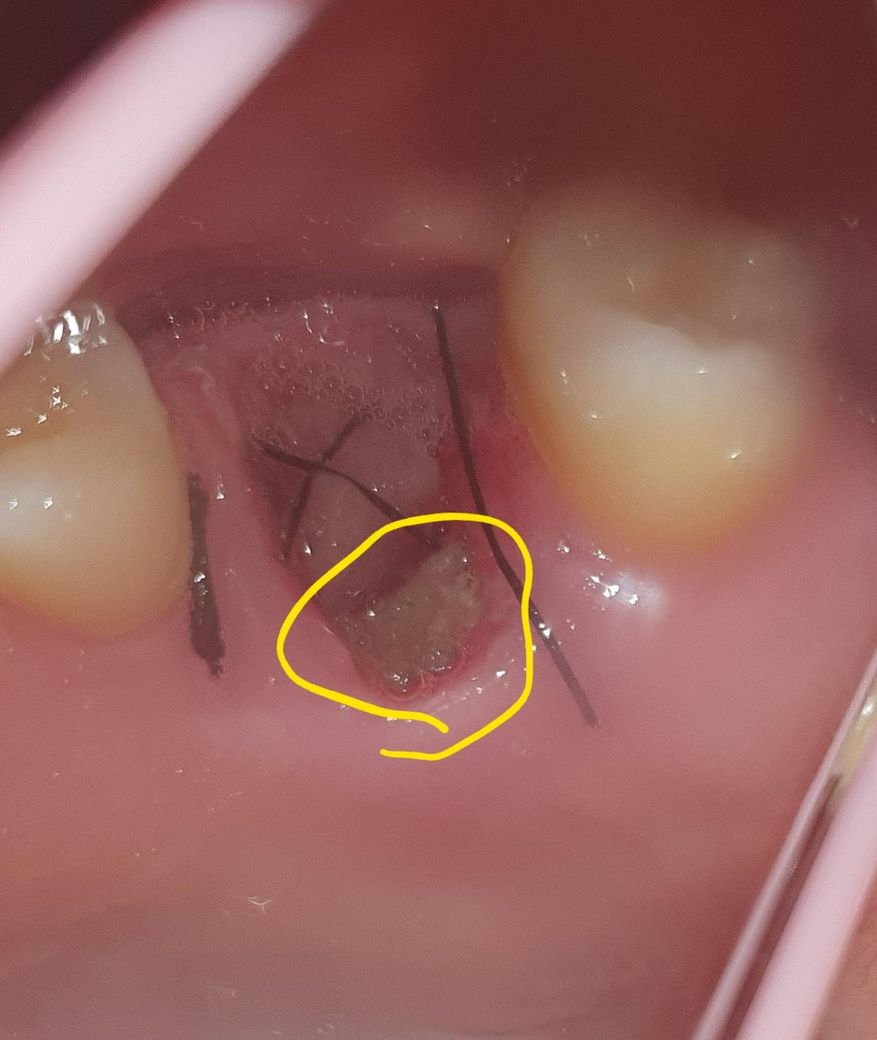

어금니발치 부위 음식물 끼임 어떻게하나요?ㅠ

떡을 반대쪽 치아로 먹긴했는데 발치한 부위로도 넘어가서 발치한 부위에 들어가서 빠지질않아요ㅠ

덩어리가 좀 큰데 떡이라 그런지 물로 헹궈도 안빠지는데 이쑤시개로 살살 빼야할까요?ㅠ

시간상으론 하루가 안됐는데 피떡?이 있어야 좋다고 들었는데 전 피떡이 없는데 잘못 관리하고있는건가요?

• 1번 째 사진

사진상으로는 문제가 없어보입니다. 음식물은 주사기에 식염수를 넣어 헹궈 빼주시는 게 좋습니다.